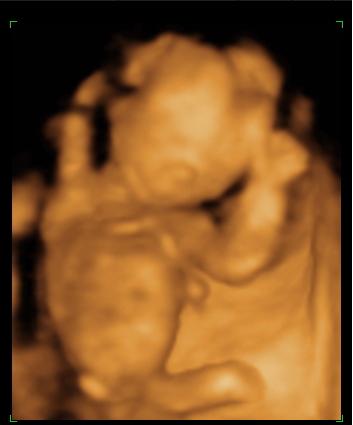

Szelina szeptember 19-én született 11.40-kor, 3700 grammal és 54 centivel. 5 napot ráhúzott a kiírásra. Jól vagyunk.

Dobok pár képet: